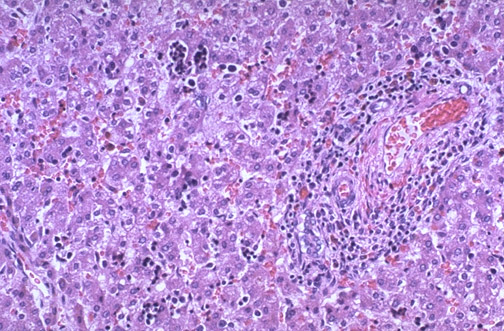

This is normal fetal liver at medium power demonstrating that at term there are islands of extramedullary hematopoiesis along with the liver cords. Note the triad to the right